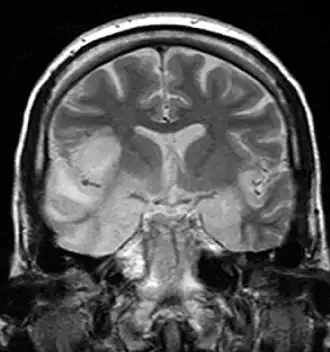

| Герпетический энцефалит | Герпетическая инфекция мозга, которая, как предполагается, вызывается ретроградной передачей вируса по аксону тройничного нерва в мозг. HSV является наиболее распространённой причиной вирусного энцефалита. Вирус накапливается преимущественно в височных долях[10]. | ![]() |